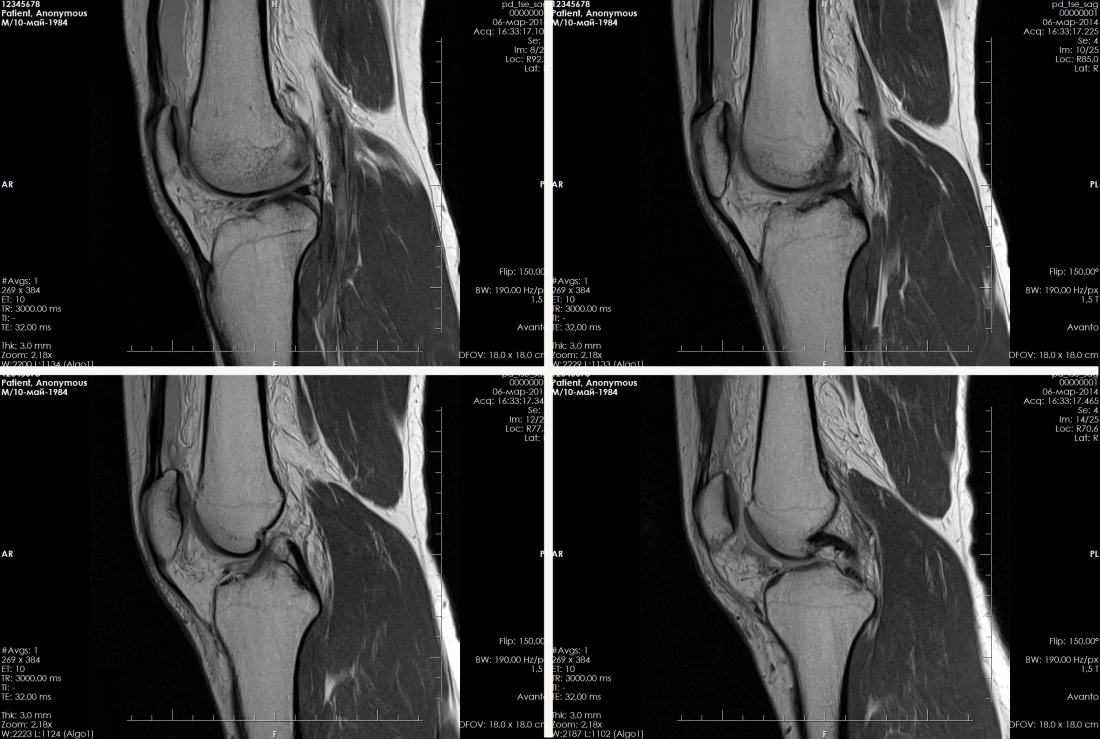

Вывих коленного сустава — болезненная травма, сопровождающаяся повреждением капсульно-связочного аппарата. Он может быть свежим (впервые полученным) или привычным (периодически повторяющимся, часто с полным разрывом передней крестообразной связки).

МРТ коленного сустава выполняется в трех взаимно перпендикулярных плоскостях, что позволяет выявить изменения, такие как повреждения внутрисуставного хряща, капсульно-связочного аппарата, менисков, ушиб костного мозга и околосуставных мягких тканей.